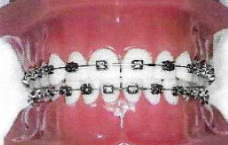

ΑΚΙΝΗΤΟΙ ΜΗΧΑΝΙΣΜΟΙ

Προσφέρονται για ακριβή, τρισδιάσταση και πολύπλοκη οδοντική μετακίνηση.

Αυτόδετα μεταλλικά

Αυτόδετα κεραμικά

Κλασσικά μεταλλικά ή κεραμικά